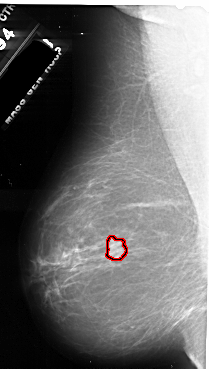

FILE: A_1055_1.LEFT_CC.OVERLAY

TOTAL_ABNORMALITIES 1

ABNORMALITY 1

LESION_TYPE MASS SHAPE IRREGULAR MARGINS SPICULATED

ASSESSMENT 5

SUBTLETY 5

PATHOLOGY MALIGNANT

TOTAL_OUTLINES 1

BOUNDARY